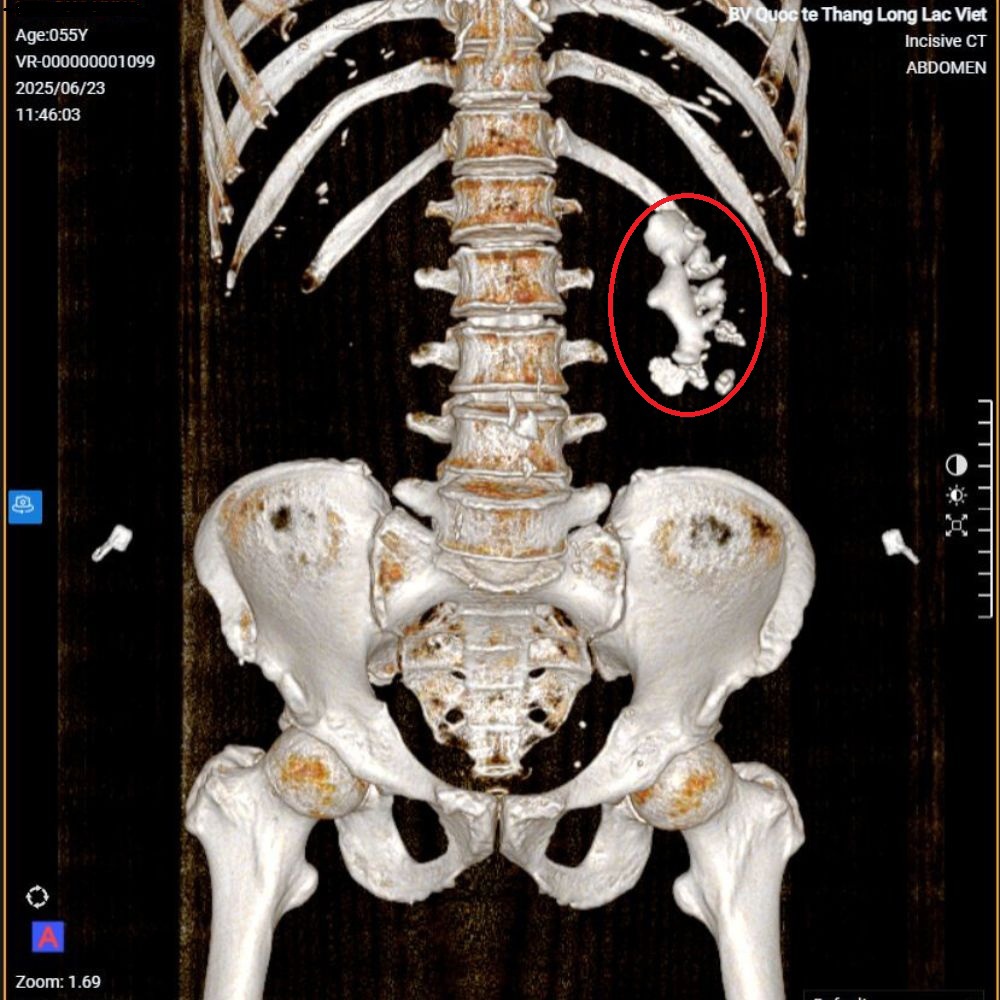

Một viên sỏi “to như củ gừng”, kích thước 6x3cm, nằm trong thận trái suốt thời gian dài nhưng chú N.Đ.H (55 tuổi) không hề hay biết – cho đến khi tình cờ đi kiểm tra sức khỏe tại Bệnh viện Quốc tế Thăng Long Lạc Việt.

Chú H. chia sẻ với BSCKI. Hoàng Văn Huấn khi thăm khám rằng chú hay bị đau mỏi vùng thắt lưng trái, kèm tiểu ra máu. Sau đó, chú H. được chỉ định chụp cắt lớp vi tính ổ bụng để kiểm tra và kết quả khiến ai cũng bất ngờ: một viên sỏi san hô kích thước lớn đang chiếm gần hết thận trái.

Hình ảnh chụp CT cho thấy bệnh nhân có sỏi thận “to như củ gừng".